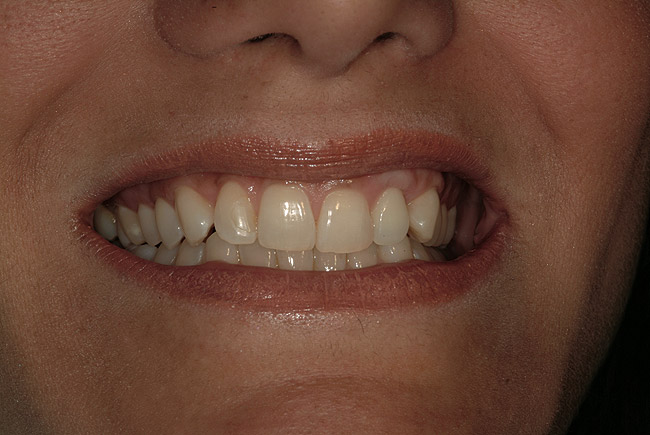

Figure 1   Localized gingival erythema and swelling associated with maxillary left lateral incisor.

Figure 1

A 34-year-old woman presented with a chief complaint of mild discomfort and swelling associated with the maxillary left lateral incisor. The patient reported a history of root canal therapy and crown performed approximately 10 years earlier. Findings from the clinical examination revealed a localized buccal gingival swelling at the level of the mucogingival junction distal to the lateral incisor, with a 9-mm probing depth on the direct facial of the tooth (Figure 1 ). Observations from the radiographic examination demonstrated a periradicular radiolucency but suggested normal interdental bone levels (Figure 2 ). Surgical exposure following flap elevation exposed a 10-mm dehiscence defect of the buccal plate (Figure 3 ), which was consistent with a vertical root fracture and hopeless prognosis. The lateral incisor was extracted to minimize the loss of alveolar bone and this was followed by thorough degranulation of the socket. Particulate FDBA saturated with rhPDGF-BB for 10 minutes was then applied to augment the deficient ridge in preparation for future implant placement (Figure 4 ). The extraction site was developed to approximate the contours of the adjacent alveolar ridge. Then, a resorbable collagen membrane (Bio-Gide®, Osteohealth) was placed over the graft to facilitate graft containment and maintenance of desired alveolar contours (Figure 5 ). Placement of the membrane without disruption or displacement of the graft during completion of the surgical procedure and suturing is critical to ensure clot formation that will support bone formation.